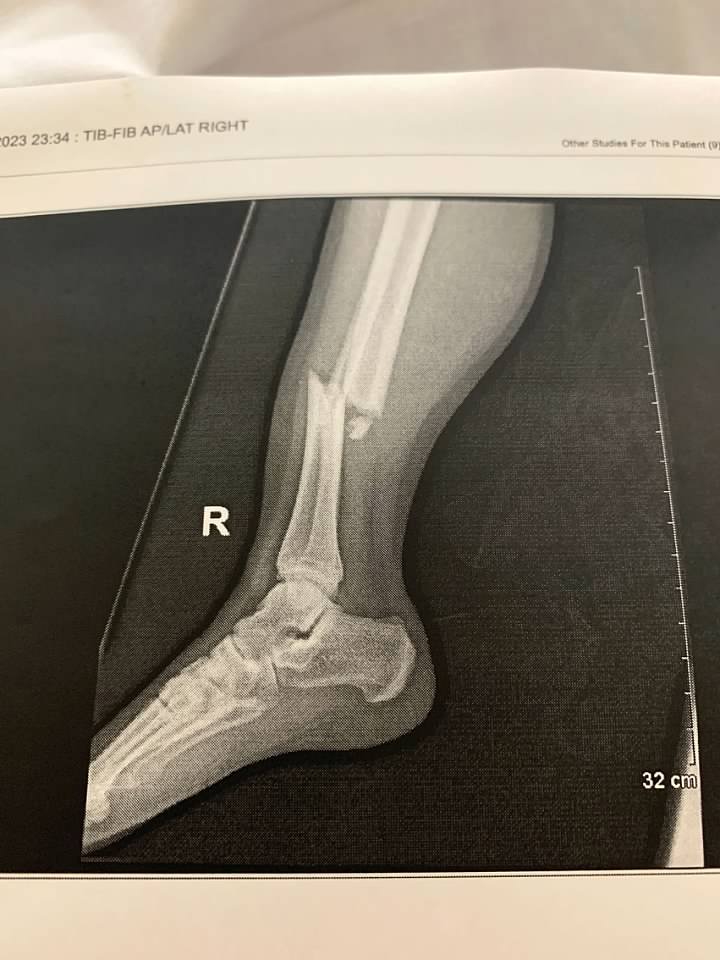

And this is the tib fib fracture on the right leg.  You can tell why his right leg is classified as non-load bearing for 6-8 weeks.  He won't be able to put ANY weight on this one for that long while it heals.  OUCH is all I can say.